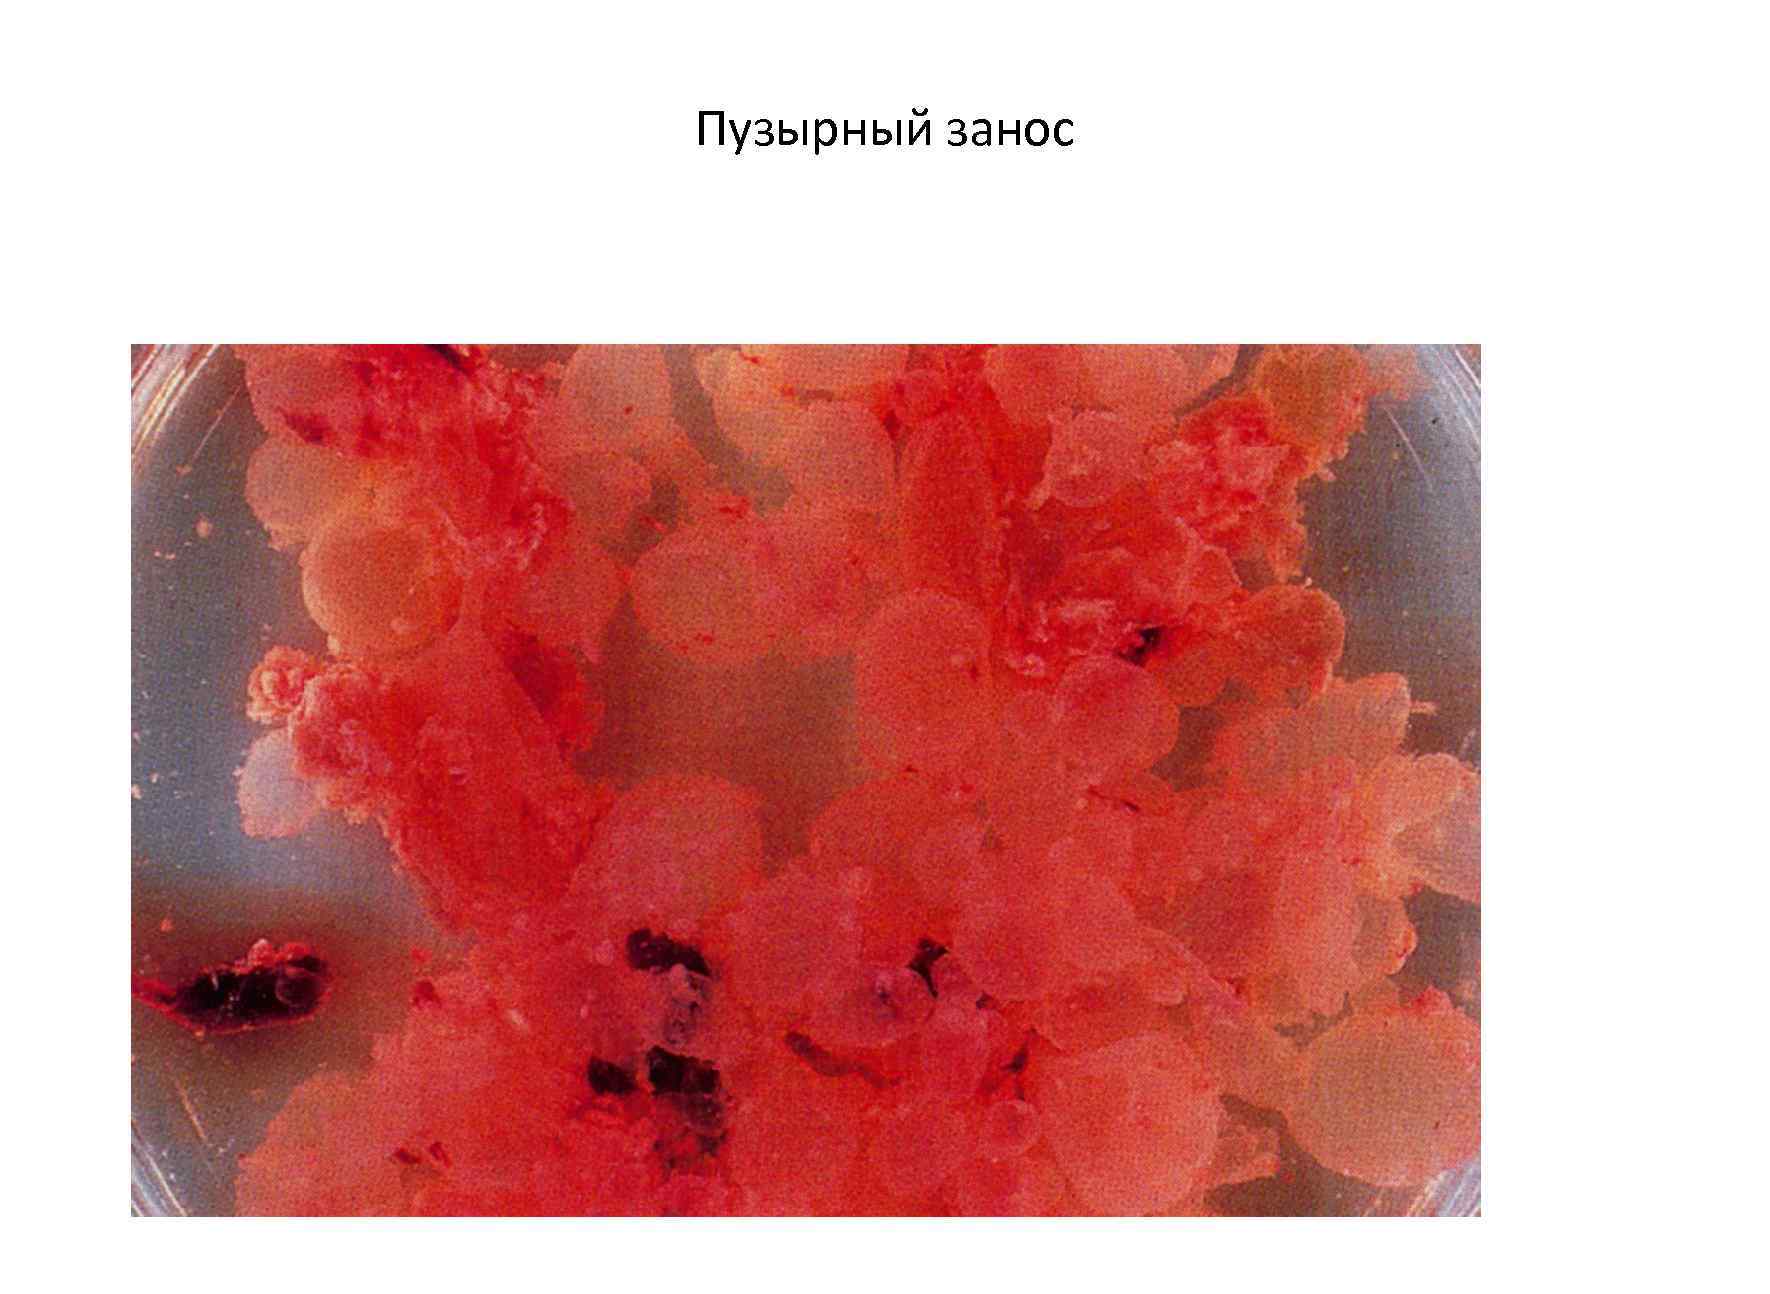

Медицина и диагностика: Инвазивный пузырный занос на УЗИ

Раздел: Альбом идей